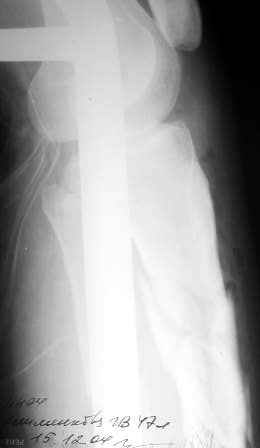

Компоновка аппарата Рис 3,4 (В проксимальной опоре фиксация спицами с напайкой, в дистальной опоре базовое кольцо- спицами репонирующее кольцо -стержнем)

закрытая репозиция. (ЭОП отсутствует) Компоновка аппарата Рис 3,4 (В

Спицевой АВФ. Закрытая репозиция, ЭОП не нужен, достаточно будет одной контрольной рентгенографии в <середине> операции.

На снимке не видно, как далеко по диафизу идет линия перелома. На мой взгляд, лучше сделать еще один снимок, как бы не пришлось делать АВФ из 4

опор.